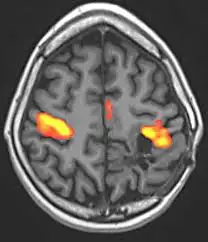

첫 번째는 우리가 잘 알고 있는 기능적 자기공명 영상(fMRI)이다. fMRI는 아주 정확하게 뇌의 구조와 반응을 볼 수 있고, 뇌에 무언가를 삽입할 필요가 없는 비침습 방식이다. 하지만 거대한 자기 코일을 사용하기 때문에 부피가 엄청나게 크고, 가격도 수십억 원에 달한다. 연구용으로 사용할 수는 있지만, 소비자들이 쓸 수 있는 인터페이스로 만들기에는 무리가 있다.

버클리 대학교의 캘런트 박사 팀은 고해상도 MRI 기술을 개발해서 사람이 어떤 영상을 볼 때 뇌의 패턴을 기록했다. 그러고 나서 MRI로 측정한 뇌의 패턴과 실제로 그 사람이 본 영상의 관계를 추적하는 수학 공식을 개발했다. 예를 들어, 어떤 사람이 사과 그림을 보고, 뇌의 모양이 ABCD로 변했다. 이제 윤곽선이 조금 다른 사과 그림을 보여준다. 그때 뇌의 패턴이 BBCD가 되었다면, 패턴 B가 윤곽선 인식과 관련되어있음을 알 수 있다. 이런 식으로 계속해서 다른 그림과 영상을 보여주고 뇌의 패턴을 기록하면, 뇌의 패턴을 그림으로 변환시킬 수 있는 공식을 추론할 수 있다.